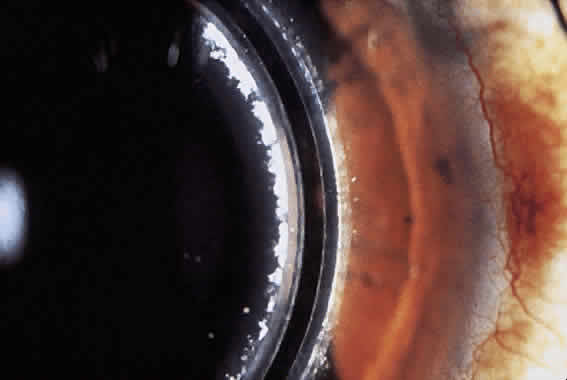

Another complication noted after surgery is epithelial ingrowth (Fig. 9). Controversy exists as to the exact cause, and thus terminology, of epithelial nests in the LASIK interface. One theory supports the idea that epithelium is caught on the keratectomy blade and planted in the interface (epithelial growth). Another possible explanation is that the epithelial cells migrate from the junction of flap (ingrowth).115 Whichever the case, the epithelial nests can proliferate, causing decreased vision secondary to obscuration of the visual axis or induction of irregular astigmatism.

Fig. 9. Slit-lamp photograph of epithelial nests in the corneal interface after laser in situ keratomileusis enhancement. A. This nest of epithelial cells were observed and exhibited no growth and no reduction of BSCVA. B. These nests demonstrated progression toward the visual axis and several attempts were made to remove them. Finally, after absolute alcohol treatment and scraping, the nests resolved. Final uncorrected visual acuity was 20/200, and best corrected acuity was 20/20 with a refraction of + 2.75 + 1.75 × 110.

Rates of epithelial growth in the interface have ranged from 1% to 10%.43,116–118 Both Perez-Santonja118,119 and Stulting43 and their associates demonstrated a low incidence of epithelium in the interface after primary treatment. They also saw an increased rate of ingrowth (up to 32%) after a retreatment. Removal of the epithelial cells is indicated if there is significant vision loss due to irregular astigmatism or obstruction of the visual axis. The epithelial cells can be removed by lifting the flap and scraping the cells from the interface. Recalcitrant cases often need repeated scrapings, sometimes with the administration of absolute alcohol or excimer laser to kill the epithelial cells. Often, peripheral epithelial nests can be observed, but they may cause flap necrosis directly over the nests.119 Any sign of growth toward the visual axis should precipitate surgical intervention.